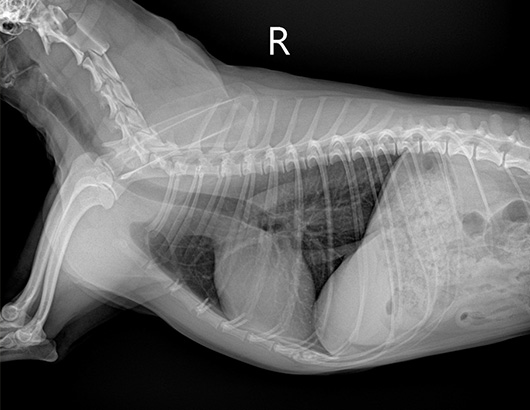

心拡大のレントゲン

病気の初期には心雑音以外の症状はありませんが、進行すると心拡大が起こり咳が出たり、疲れやすくなります。さらに進行すると肺水腫をおこし咳や呼吸困難に陥り死亡してしまいます。

僧帽弁閉鎖不全症についてはガイドラインが広く知られていて、重症度判定とそれに応じた治療指針が提唱されています。その中で投薬による治療対象となるのは、僧帽弁閉鎖不全症により心臓に明らかな拡大が認められる場合です。心臓の拡大はレントゲン検査と心エコー検査で判定します。薬を飲むことで病気自体が治るわけではありませんが、時期を見定めてしっかりと投薬治療を開始することで病気の進行を遅らせ、延命することが可能です。